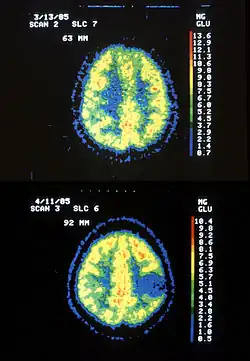

Astrocytom je typ rakoviny mozku, který vzniká v astrocytu, neboli gliové buňce v cerebru. Tento tumor se nemetastazuje mimo mozek a míchu. Jde o nejčastější formu gliomu, častěji v mozku, zřídka v míše. Formy šíření se dělí na: